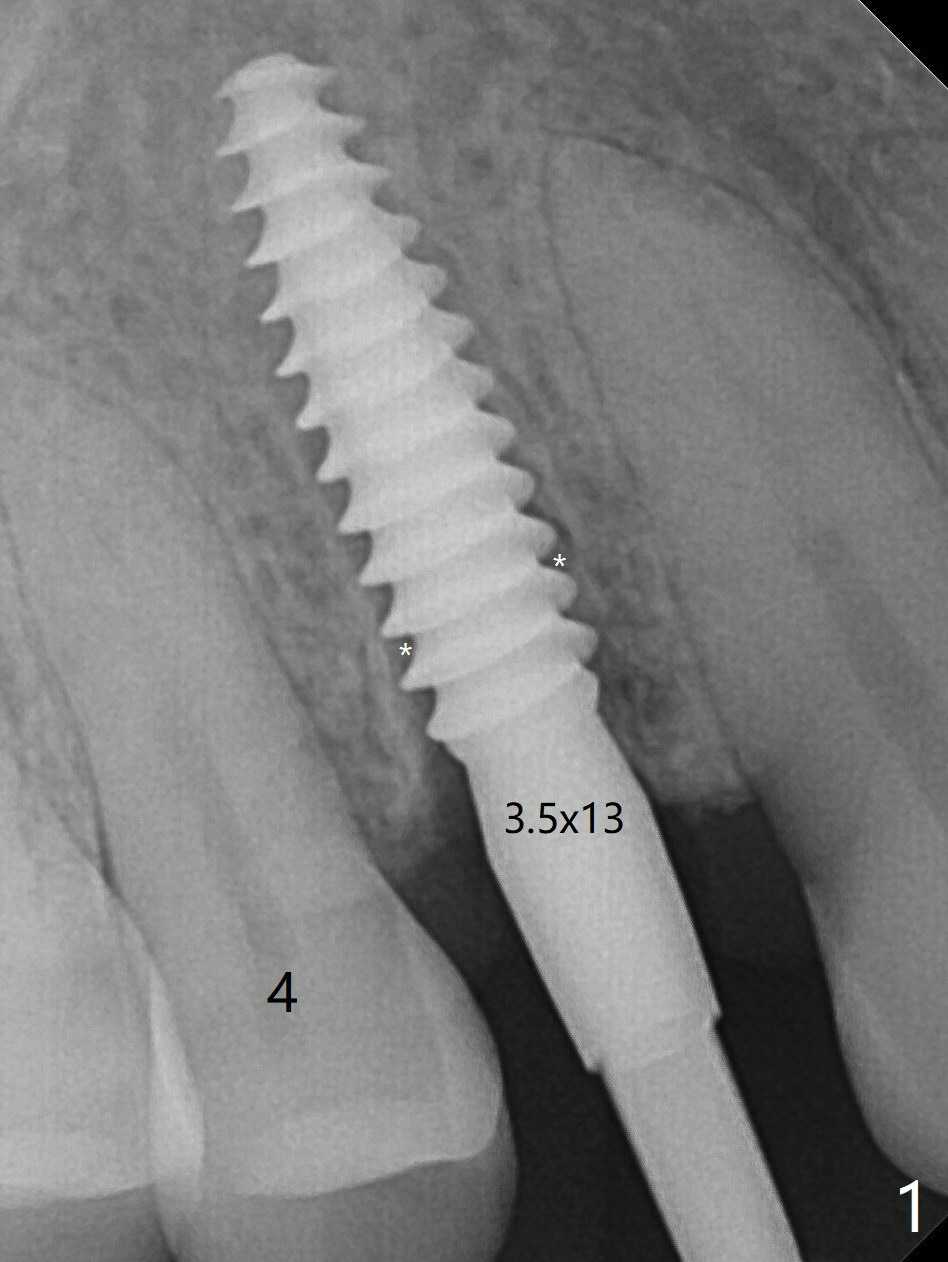

降低基台高度后(图二:箭头),用骨粉充填(图二:*)。